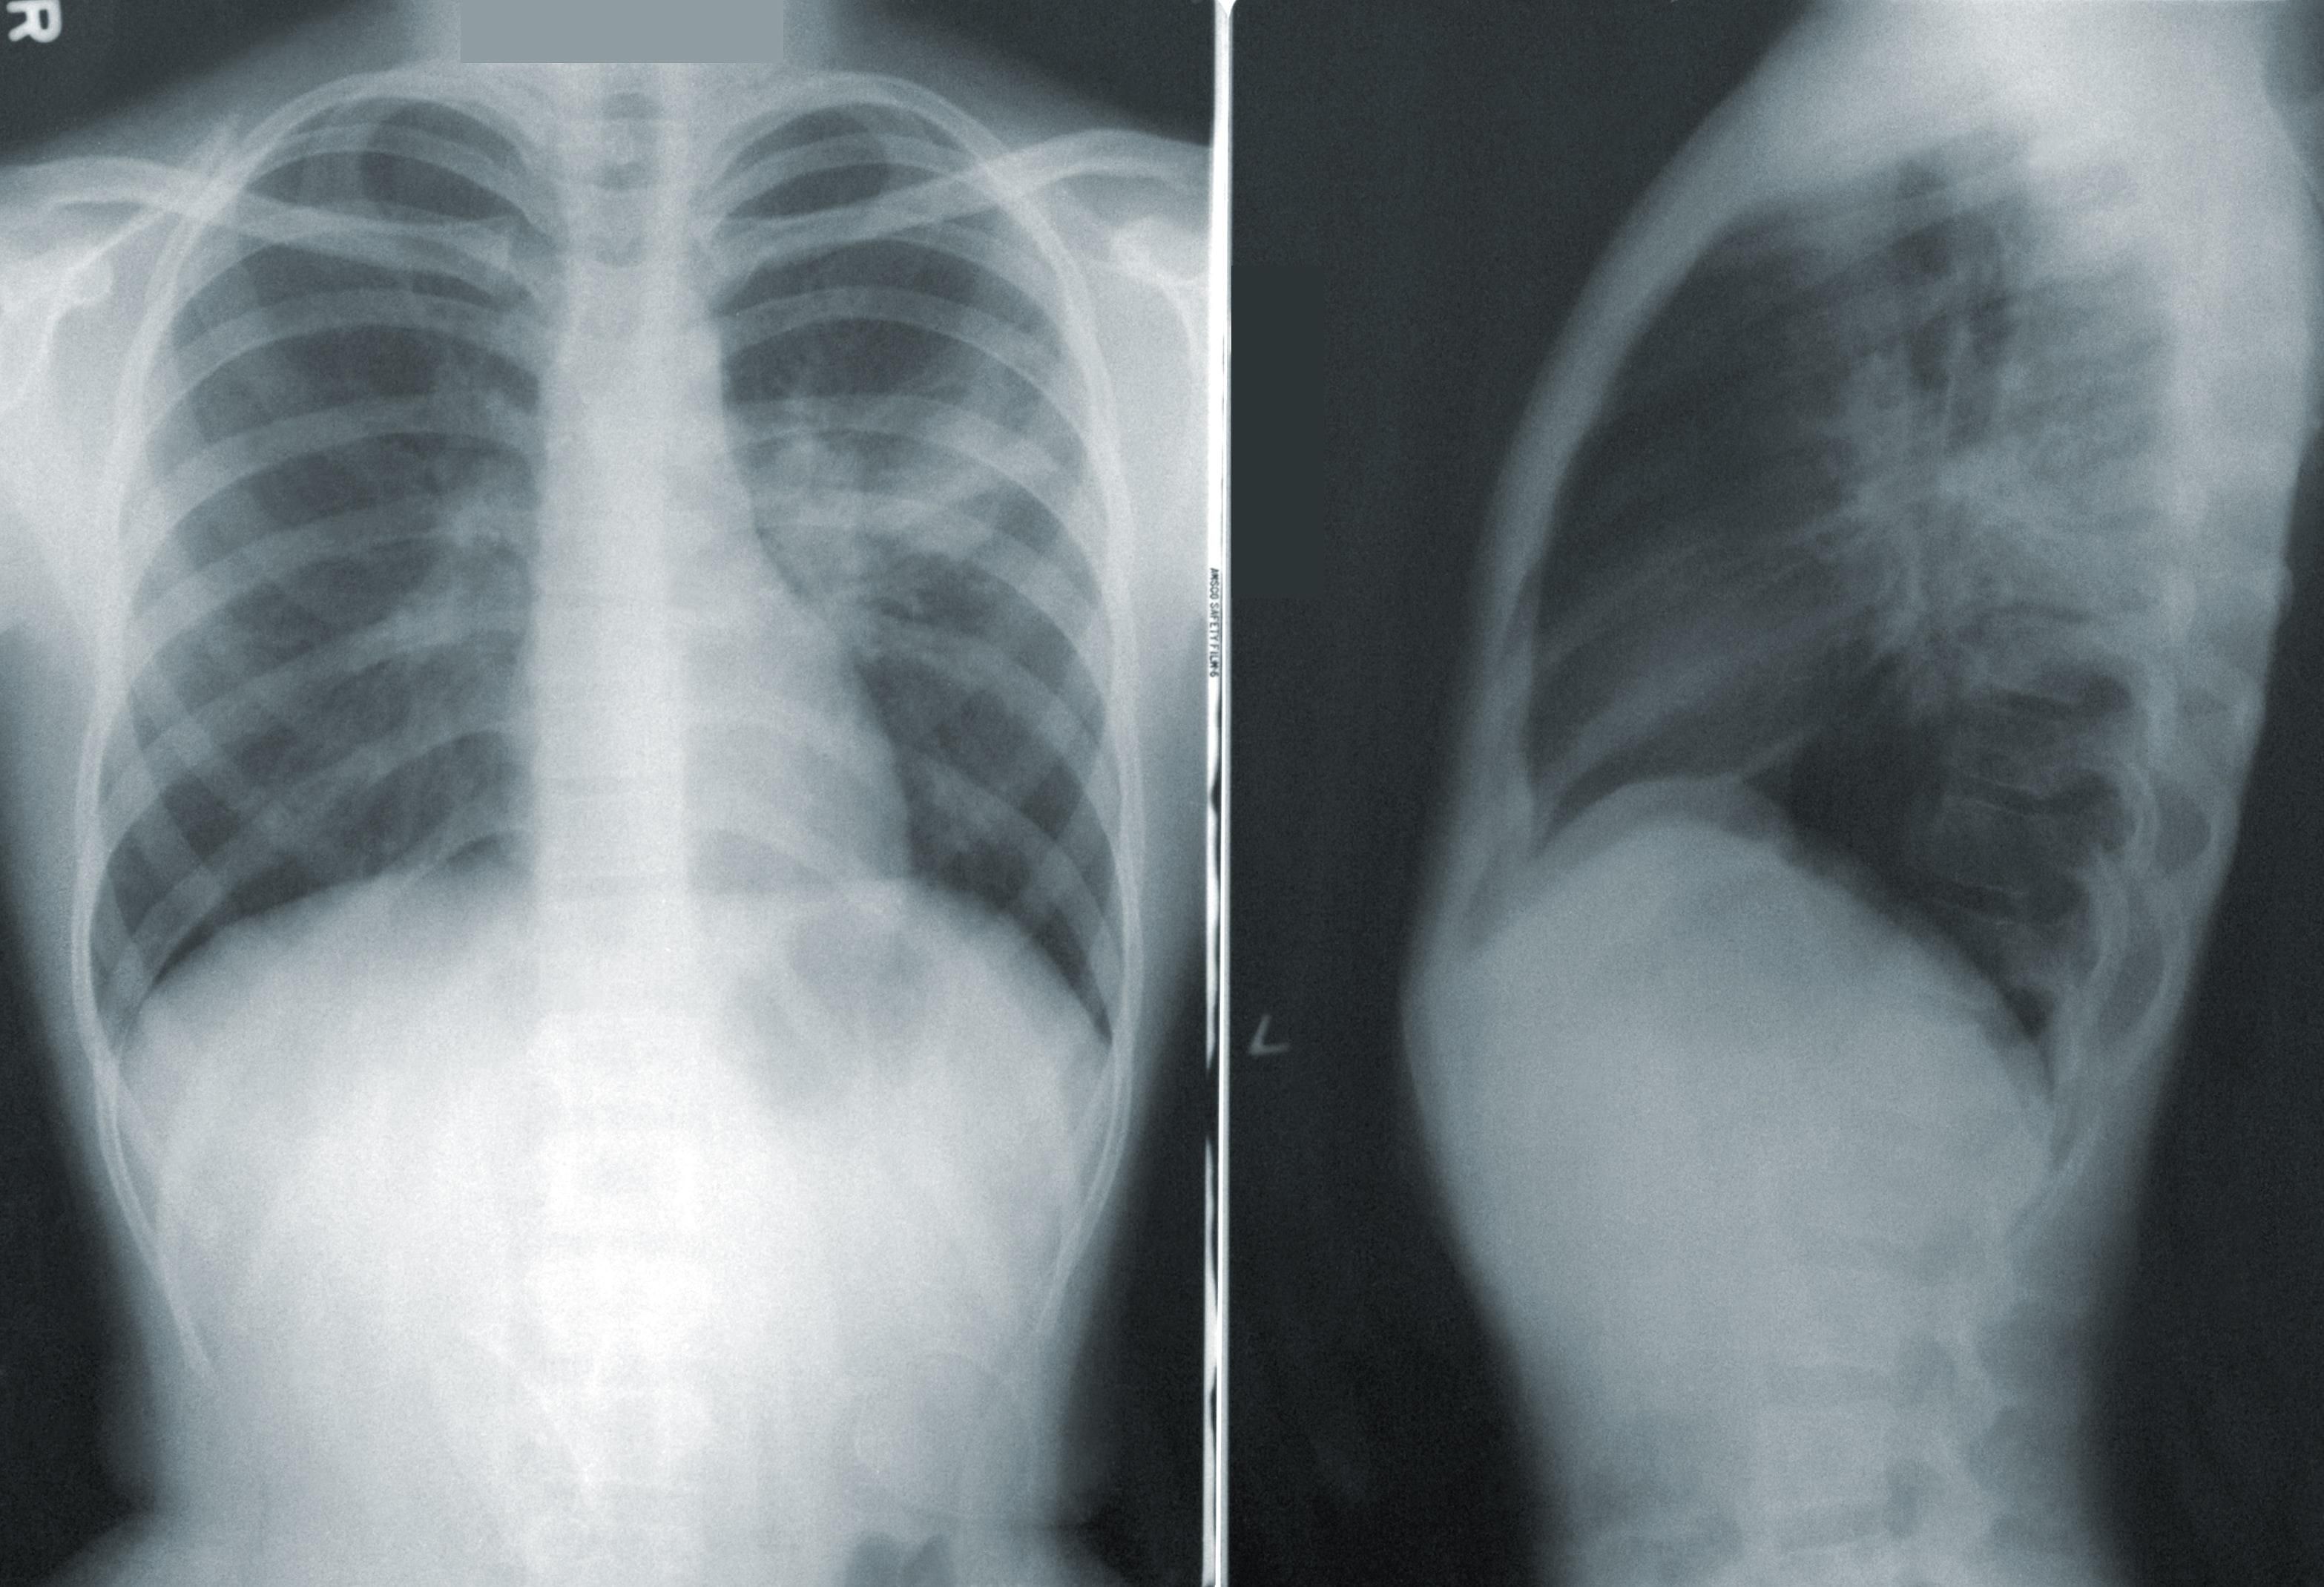

Ініціативу вирішили почати, бо рак легенів – найчастіша причина смерті серед всіх онкологічних захворювань в Чехії. Як відомо, паління є поширеною звичкою серед жителів країни. До того ж у більшості пацієнтів діагноз виявляють пізно: пацієнти часто звертаються до медиків на стадії, коли пухлина вже не може бути прооперована.

Лікарі зв'яжуться з теперішніми або колишніми курцями у віці від 55 до 74 років, які використовують приблизно одну пачку цигарок на день протягом 20 років. Якщо пацієнт погодиться взяти участь у програмі, то лікар скерує його на обстеження в легеневу клініку. Після цього буде проведено скринінг з використанням комп'ютерної томографії (КТ).

За словами фахівців, обстеження нескладне і дозволяє виявити пухлину всього за кілька хвилин навіть на ранній стадії.